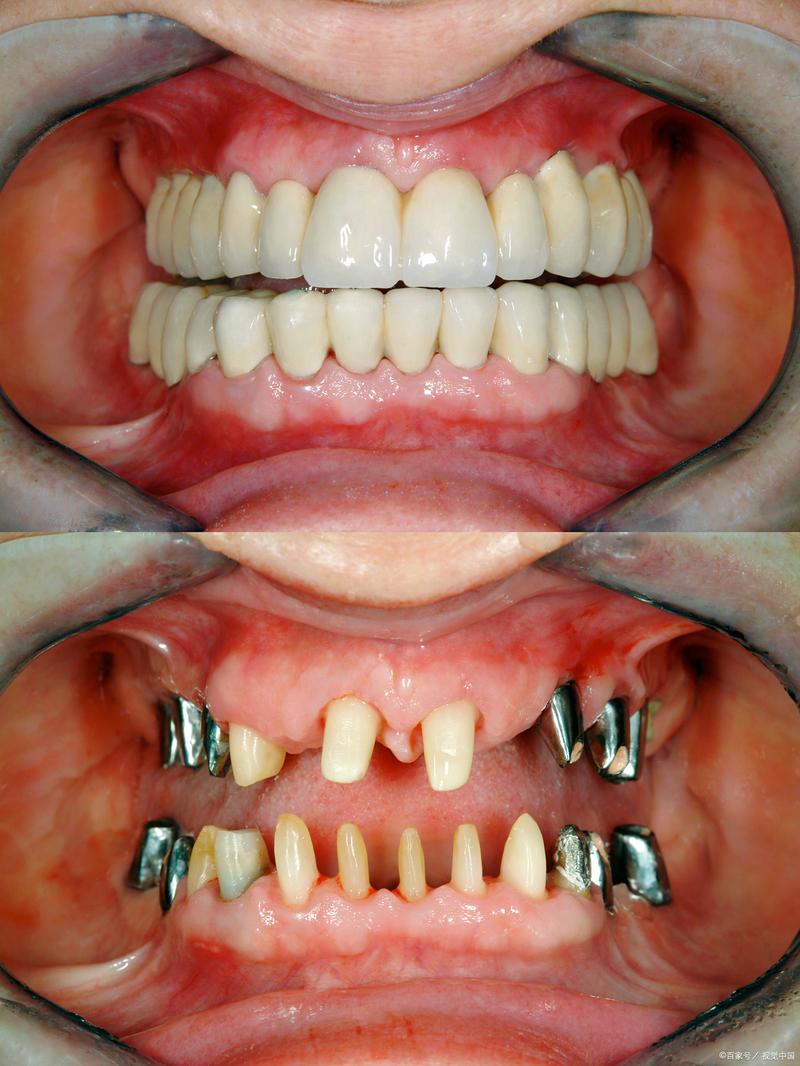

骨密度低并非种植牙的绝对禁忌症,通过术前精准评估、个体化骨增量方案选择、优化种植体设计与术后长期维护,骨密度低患者仍可获得满意的种植效果,关键在于“多学科协作”(口腔种植科、骨科、内分泌科等)与“全程化管理”,从骨质量改善到种植体稳定,再到远期并发症预防,每个环节都需精细把控,最终实现功能与美观的双重恢复。